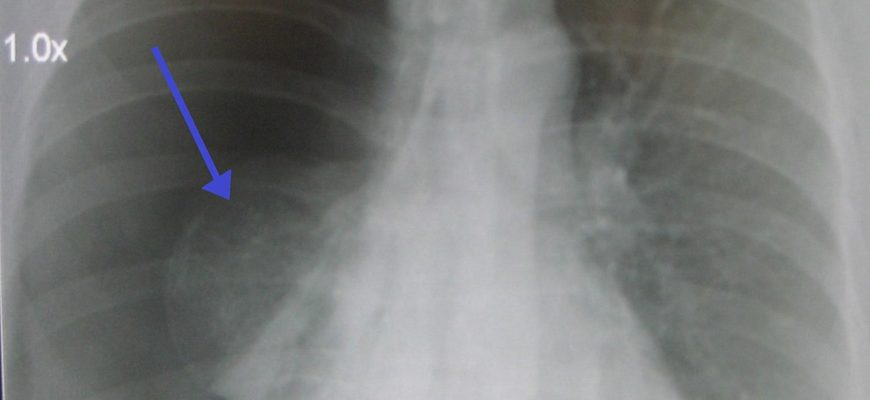

Дыра в легких — очень опасное состояние, которое может вызвать негативные последствия для здоровья. Чтобы справиться с этим расстройством и поддержать пациента, очень важно поставить точный диагноз в нужное время. Так что же это и как это относится?

Легочная ткань изготовлена из альвеол, небольших фолликулов, которые заполнены воздухом. Они занимают весь орган вместе с кровеносными сосудами и небольшими бронхами. В нормальных условиях в них не должно быть отверстий. Тем не менее, существуют ситуации, в которых дефекты образуются в органе. Ключевой задачей специалиста является определение причин их формирования.

Отверстия образуются в местах разрушения тканей. Пузырьки легких и бронхов умирают и растают, а пораженные места разделяются воспалительной насыпью. Это условие указывает на неправильные процессы, происходящие в организме. Однако их происхождение может быть другим. Общие факторы включают:

- Гулентные воспалительные изменения — гангрена, туберкулез, абсцесс;

- Узловой рост — рак на стадии разрушения;

- Системные патологии — саркоидоз;

- Паразитические заболевания — абзац, пузырь;

- Другие патологии — в частности, мочевой пузырь.